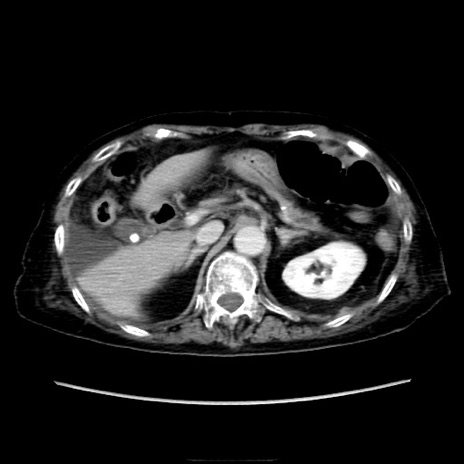

症例40(横断像)

横断像